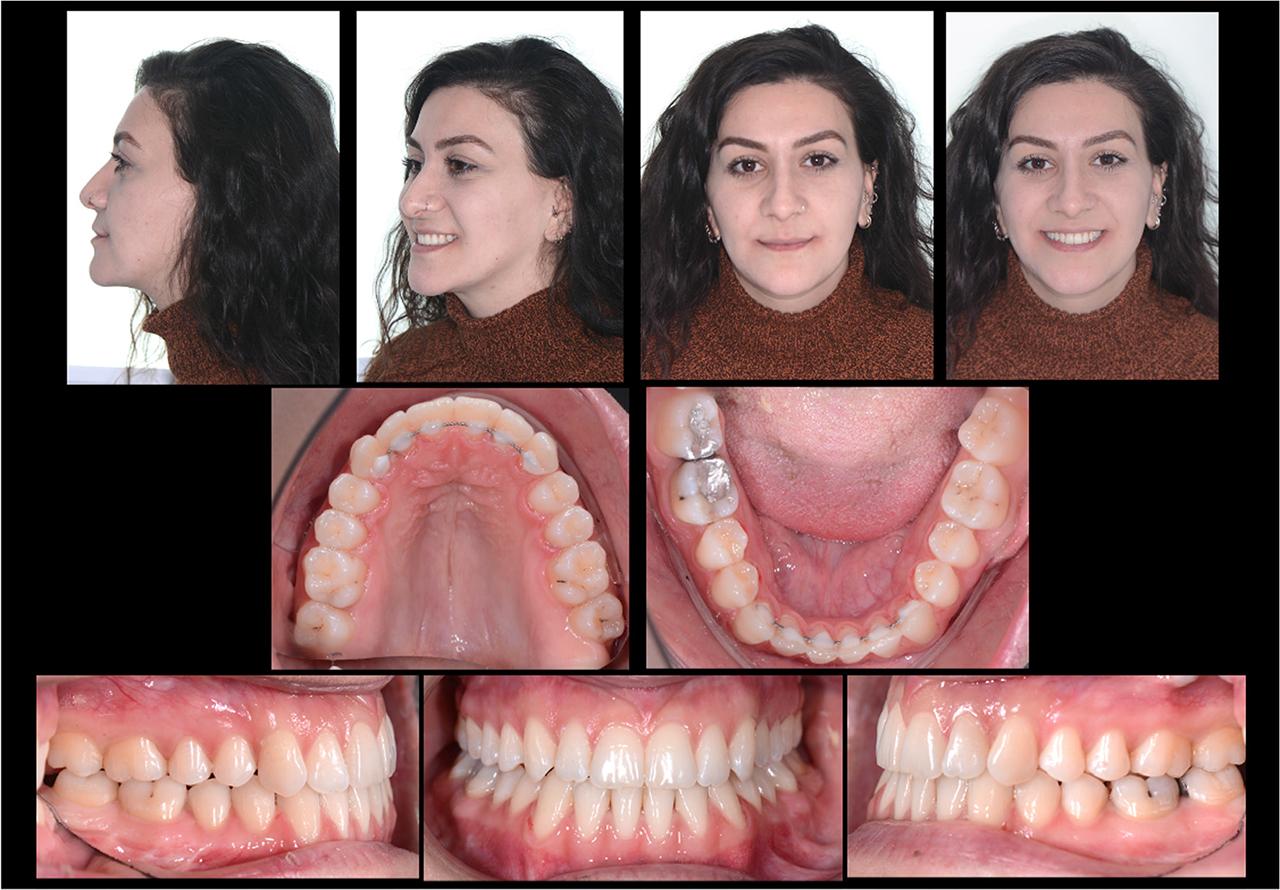

Post-treatment extraoral and intraoral photographs.

Treatment results

Post-treatment photographs in the frontal and lateral views revealed an improvement in facial aesthetics (Fig. 9). The post-treatment cephalometric analysis showed that a skeletal Class I (ANB = 2.1°) relationship was achieved (Fig. 10, Table I). The maxillary and mandibular arches were aligned, the anterior and bilateral posterior cross-bites were corrected and Class I molar and canine relationships were obtained along with an ideal overjet and overbite (Fig. 11). The mandibular midline was corrected with respect to the facial midline and an occlusion with solid intercuspation was achieved (Fig. 9).

Figure 11

Post-treatment dental casts.

The post-treatment panoramic radiograph showed no significant root resorption (Fig. 10). Upon super-imposition of the pre- and post-treatment cephalometric radiographs (Fig. 12), skeletal and dental improvement was noted. One-year post-treatment photographs and radiographs showed that the treatment results remained stable (Figs. 13 and 14). It was appreciated that the overbite and settling of the occlusion were much better at the one-year review as a result of the resolution of the anterior bite plane effect created by the lingual brackets (Figs. 13, 14 and 15).